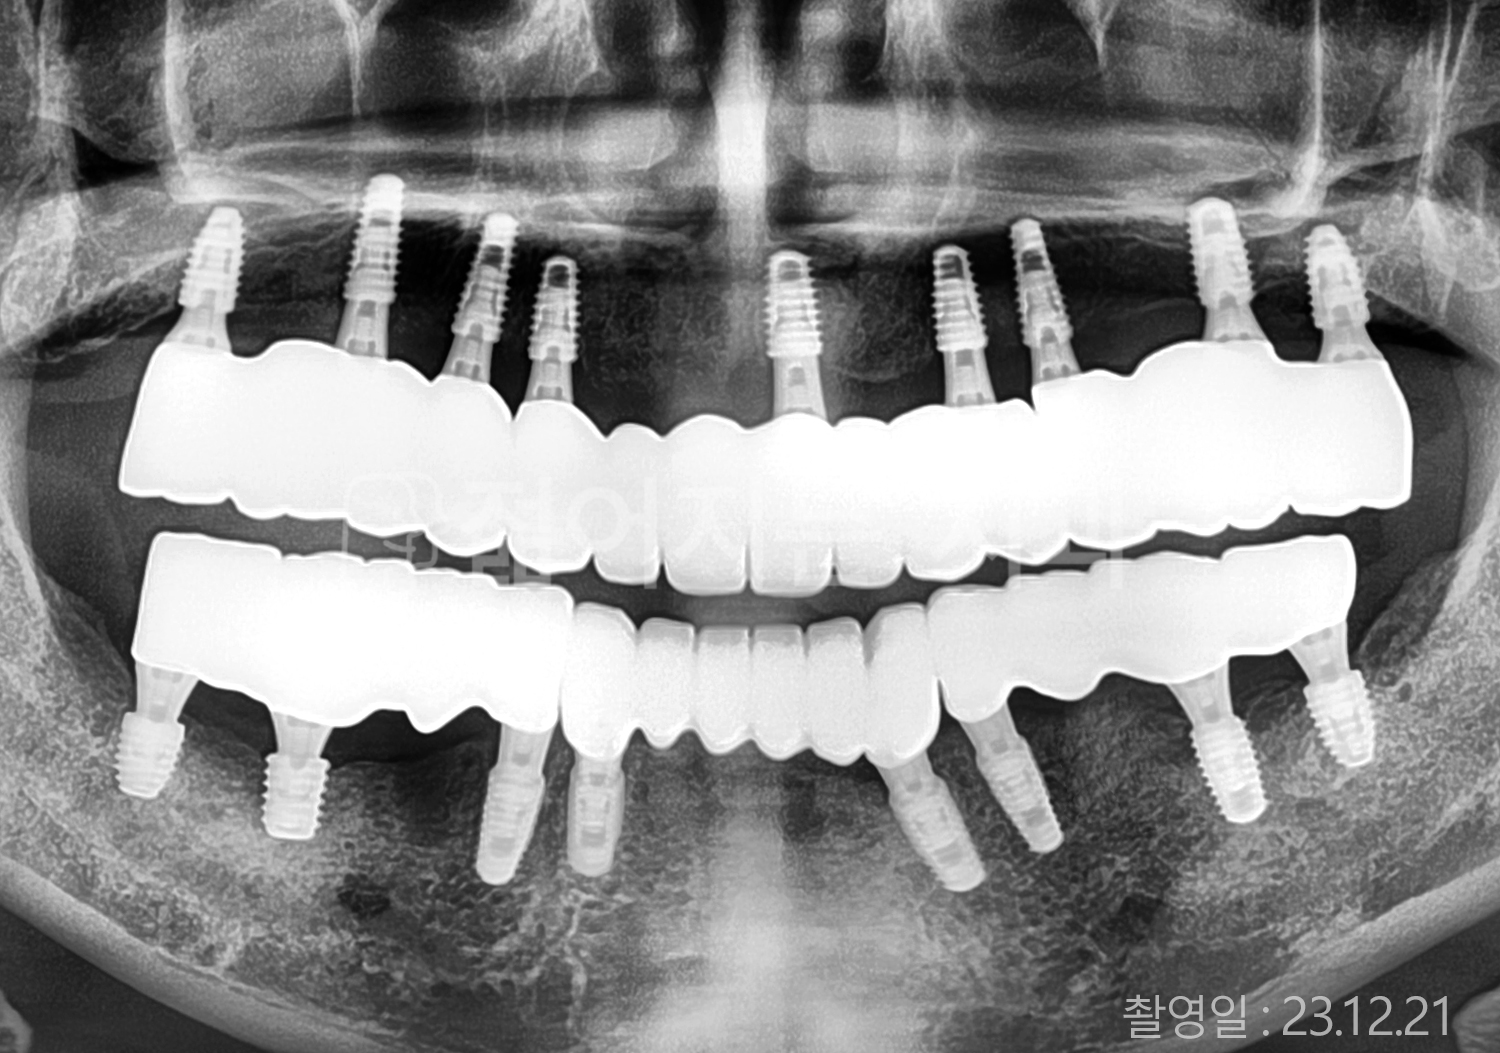

• 50대 전체치아 10개 이상 임플란트